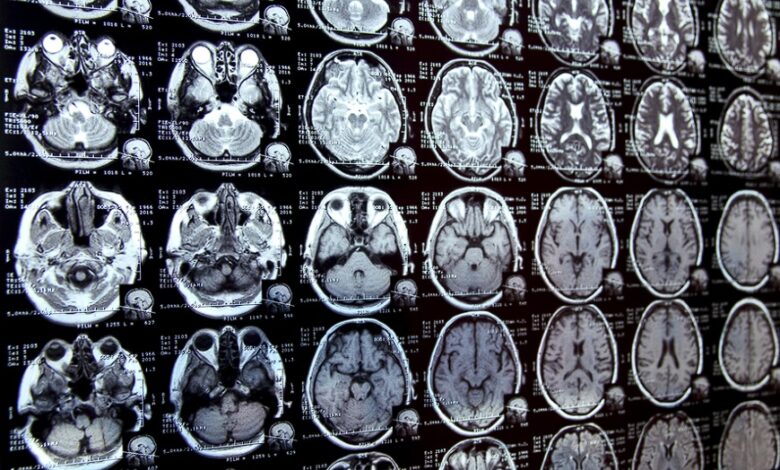

تشكل عملية ترميز وتحديد المناطق ذات الأهمية في الصور الطبية، والمعروفة باسم “التجزئة” (Segmentation)، الخطوة الأولى والأكثر تعقيداً في العديد من الدراسات السريرية الجديدة. فعلى سبيل المثال، لدراسة كيفية تغير حجم الحُصين في الدماغ مع تقدم المرضى في العمر، يتعين على الباحث أولاً تحديد وتخطيط كل حصين يدوياً في سلسلة من فحوصات الدماغ. غالباً ما تكون هذه العملية يدوية بالكامل وتستغرق وقتاً طويلاً، خاصة عندما تكون الهياكل المراد دراستها صعبة التحديد.

لتبسيط هذه العملية، ابتكر الباحثون في MIT نظاماً للذكاء الاصطناعي يتيح للباحث تجزئة مجموعات جديدة من الصور الطبية الحيوية بسرعة فائقة، من خلال النقر والخربشة ورسم مربعات على الصور. يقوم هذا النموذج الجديد باستخدام هذه التفاعلات للتنبؤ بالتجزئة المطلوبة.